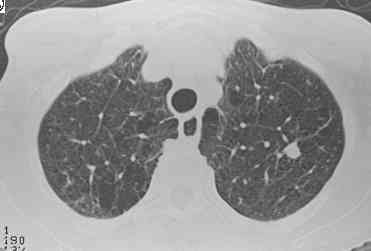

CT Scans: chest Xray versus CT, chest Xray versus CT,

Xray versus CT, CT small left lung nodule, CT